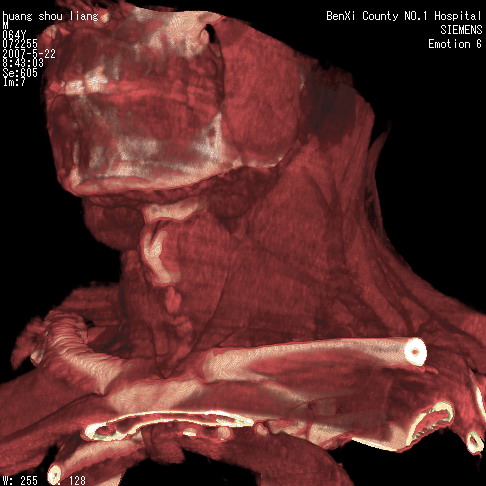

男性,64岁。颈部包块8年。最近增大。

对不起大家,可能是片子发太多有点乱,正常腮腺在下颌角的外侧,颌下腺在下颌体的中部内侧,本例在下颌角内侧偏下,和腺体一点关系都没有,从vrt和mpr上可以很明显看出来,再者肿块是好多粘连在一块的,大家在仔细看看,左侧可能也是吧,我还是考虑为肿大的淋巴结融合在一块,但性质??????

多考虑颌下腺混合瘤恶变,建议进一步检查,另外楼主重建图像很漂亮。

大家好,病理结果出来了,如大家所说,颌下腺混合瘤。